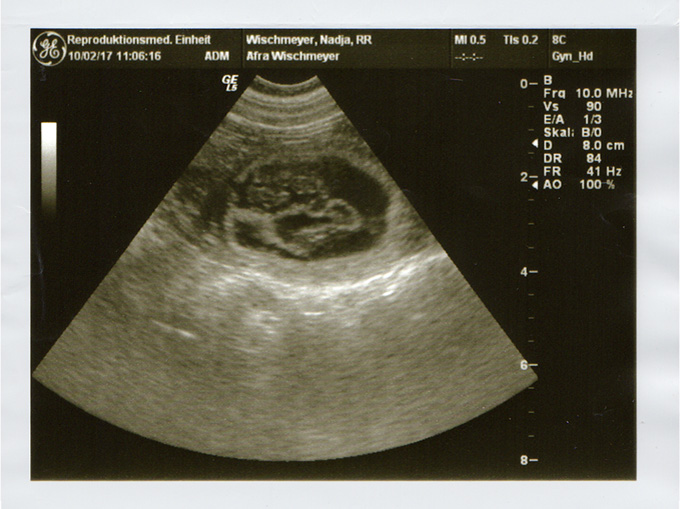

Die Ultraschall-Untersuchung hat es bestätigt: Blankas und Oubaas Treffen wird Früchte tragen. Wir erwarten die Welpen um den 20. Mai herum.

Die Ultraschall-Untersuchung in der zweiten Februarwoche hat es bestätigt: Afras Besuch bei Bhanu wird Früchte tragen. Wir erwarten die Welpen um den 14. März herum. Sollte Sie Interesse an einem Welpen aus unserer Zucht haben, freuen wir uns über eine frühzeitige Kontaktaufnahme.